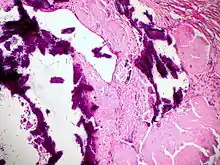

![]() LANGHANS-Riesenzellen in einem Tbc-Granulom, transbronchiale Biopsie |

![]() Fremdkörper-Riesenzellen bei Aspirationspneumonie, Autopsiepräparat, H&E. |

![]() Riesenzelle und diffuser Alveolarschaden bei SARS-Infektion. |

![]() Riesenzelle mit intrazytoplasmischen inclusion bodies bei Masernpneumonie, Histopathologie. |